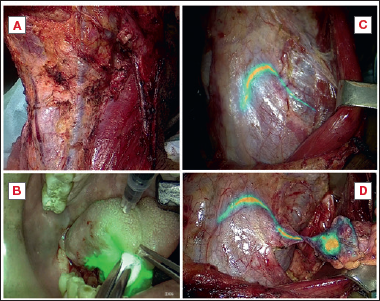

Following subplatismal flap harvesting, we intraoperatively performed 3 to 4 submucosal/peritumoral injections of 1-2 ml at 5 mg/ml of ICG (Fig. 2). ICG (ICG-Pulsion; Pulsion Medical Systems) has been previously prepared as powder suspension into sterile water for injectable solutions at a weight/volume ratio of 5 mg/ml.

Once injected, the ICG allowed to obtain NIR reflectance fluorescence imaging through the use of PDE (Neo, Hamamatsu Photonics, Hamamatsu, Japan) or directly on a monitor (Exoscope Storz OPAL1, Karl Storz), and to follow the transcutaneous course of the tumoural lymphatic drainage (up to 3 cm of depth).

Once the ICG has reached cervical lymphatic pathways (approximately 15-20 min later), the visual signal given by the fluorescence enables surgeons to identify the entire lymphatic network along with the enhancing and potentially pathological nodes. Similarly to the RGS, a final check of any residual fluorescence confirmed the sentinel lymph node removal.

Figure 2. Intraoperative ICG procedure. A) Incision and preparation of subplatysmal flap; B) submucosal injection of ICG in 4 cardinal peritumoral points; C) visualization of the lymphatic network; D) removal of the ICG drainage tract and lymph node.